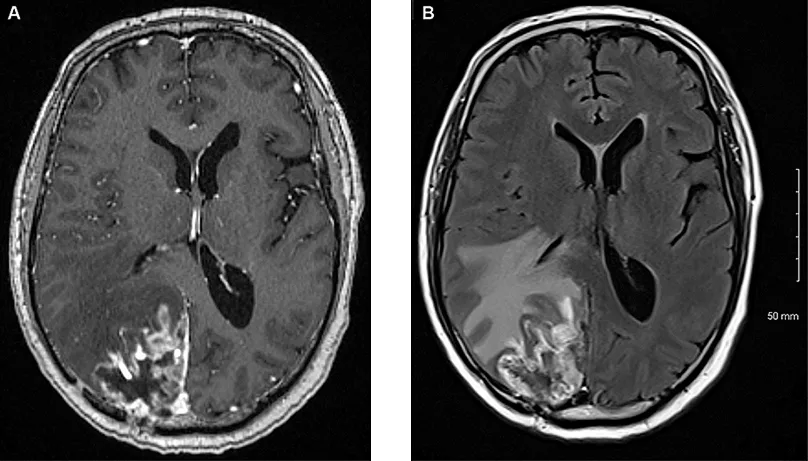

Radionécrose / Récidive

La radionécrose cérébrale (RN) est un effet secondaire complexe de la RCS, représentant un challenge diagnostique et thérapeutique, d’autant plus que la tumeur primitive est contrôlée (14). Différencier la RN de la récidive tumorale locale est fondamental et impose des modalités diagnostiques spécifiques et avancées ainsi qu’une approche multidisciplinaire. Le délai d’apparition de la RN varie entre quelques mois à quelques années après le traitement, elle se manifeste par des modifications radiologiques à l’IRM et parfois des symptômes neurologiques, lesquels peuvent correspondre à ceux d’une véritable récidive. Les principaux facteurs de risque identifiés sont le volume de cerveau irradié, la dose délivrée et les antécédents d’irradiation. Le recours à l’imagerie multimodale a démontré son intérêt en termes de précision diagnostique et aide au diagnostic différentiel. La prise en charge thérapeutique varie en fonction des symptômes. La RN asymptomatique peut relever d’une simple surveillance par une imagerie régulière, tandis que la RN symptomatique nécessite souvent une corticothérapie. Les thérapies ciblées comme le bévacizumab ont montré des résultats prometteurs dans les essais cliniques, avec une amélioration radiographique et symptomatique significative. Cette option thérapeutique fait encore à ce jour l’objet d’investigation (étude BRADI). De plus une intervention chirurgicale peut être nécessaire afin de lever des symptômes résistants au traitement d’autant plus qu’elle permet une confirmation histologique.